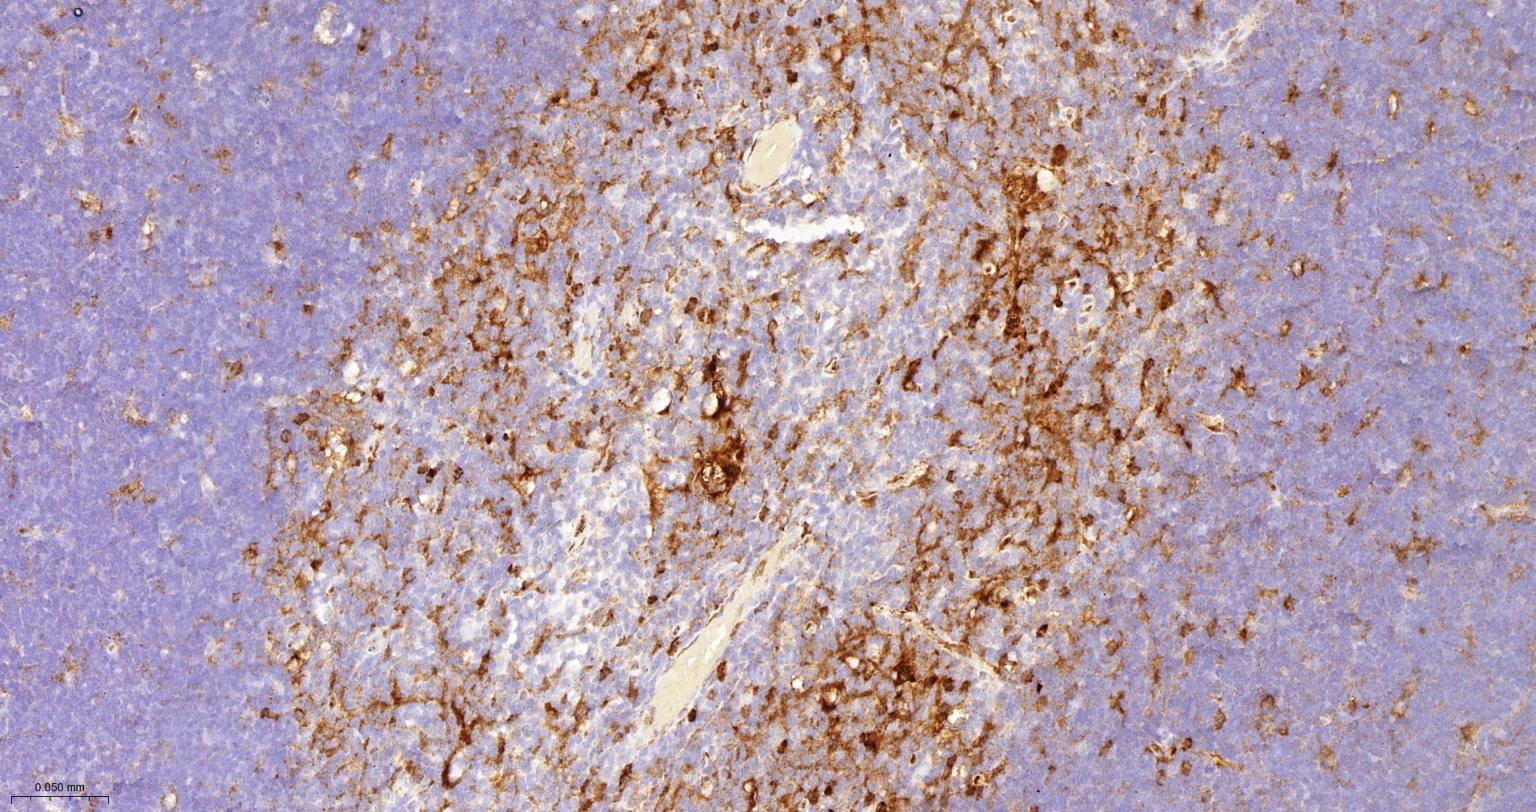

Paraformaldehyde-fixed, paraffin embedded Human Spleen; Antigen retrieval by boiling in sodium citrate buffer (pH6.0) for 15 min; Antibody incubation with CD16 Monoclonal Antibody, Unconjugated(bsm-54679R) at 1:400 overnight at 4°C, followed by conjugation to the bs-0295G-HRP and DAB (C-0010) staining.